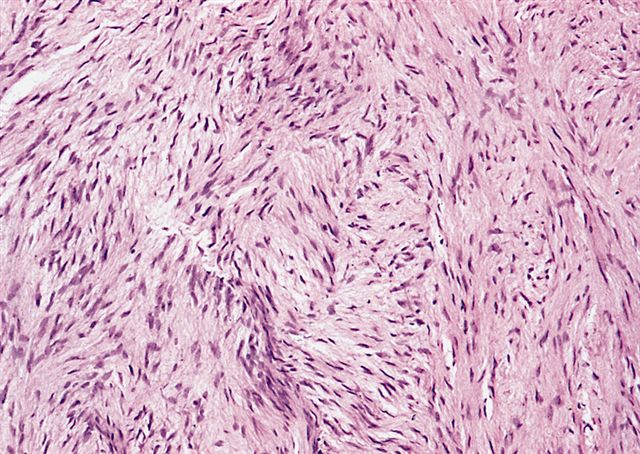

Microscopic (histologic) description

- Low to moderately cellular, bland fusiform or spindled cells with focal to diffuse whirling in heavily collagenized stroma with abrupt transition to myxoid areas

- 45% have epithelioid areas

- Occasionally has areas of increased cellularity, atypia, necrosis or mitotic activity characteristic of intermediate to high grade sarcoma

- Recurrences may show increased cellularity and mitotic activity

Microscopic (histologic) images